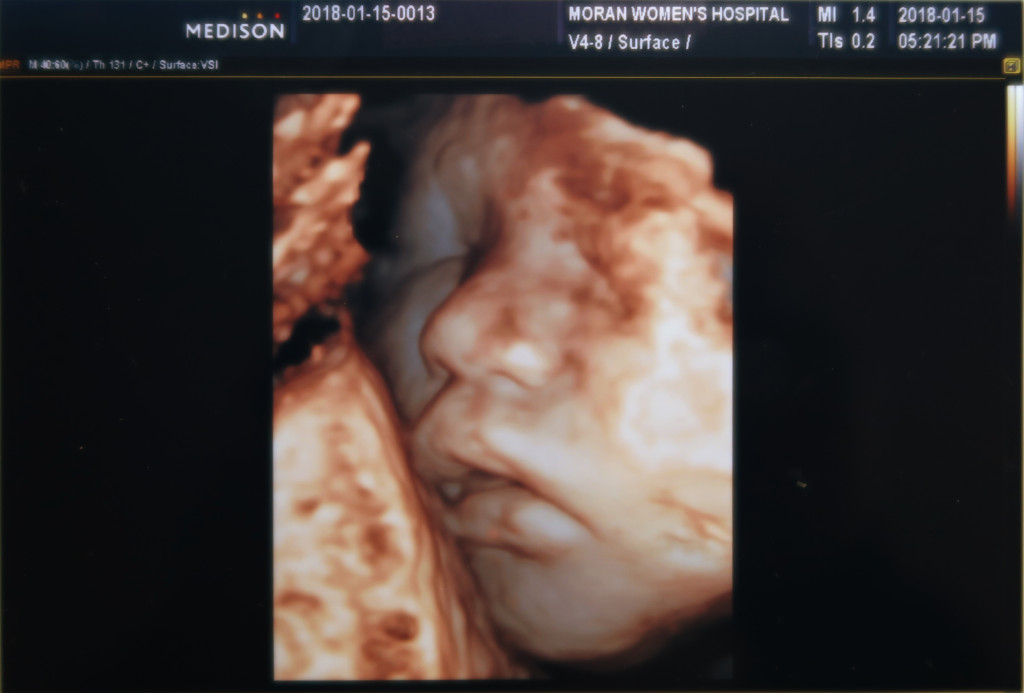

이사진은 잠자는 랑구 표정 판박이네요 ㅋㅋ

서현이 때는 아빠가 한번도 초음파 검사 하는걸 놓친적이 없는데.

이날은 서현이가 차에서 잠드는 바람에 아빠는 차에서 서현이 깨는거 기다린다고 사진만 보게 되었어요 ㅎㅎ

가운데 있는게 코고, 밑에 콧구멍 두개가 보입니다^^

아직 태어나지도 않은 아들에게 벌써 미안한 일들이 많네요.

아무래도 서현이 때는 모든게 처음이라 신기하기도 했고, 지금은 서현이 키운다고 정신이 없어서